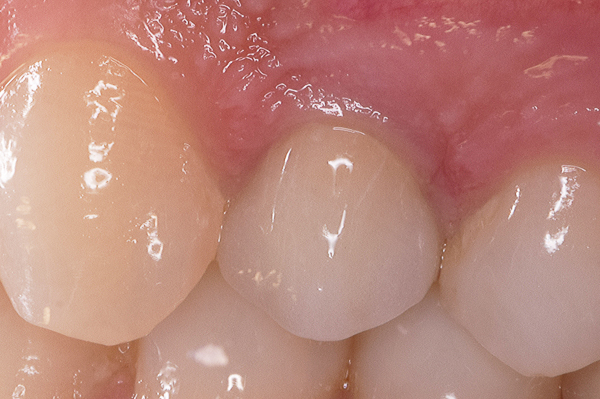

A seguito dell'analisi radiografica viene pianificata l'estrazione atraumatica del premolare con l'inserimento contestuale di un impianto Shelta. La riabilitazione immediata viene eseguita con un pilastro XA per protesi avvitata, su cui viene fissato un provvisorio realizzato in laboratorio secondo i principi dei profili di emergenza della tecnica B.O.P.T.